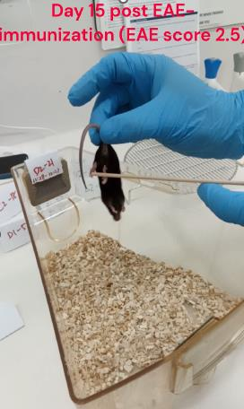

Mouse model shows remarkable improvement after treatment with DioprotectomeTM for 15 days

Day 15: The mouse exhibits MS symptoms (tail and hind limb paralysis) and was unable to walk properly

Full video is available in data room or can be accessed by scanning the QR code

Day 30 during the MS-like disease course (15 days after daily oral treatment with DioprotectomeTM): The mouse’s tail and hind-limb functions were restored and showed significant improvement in walking